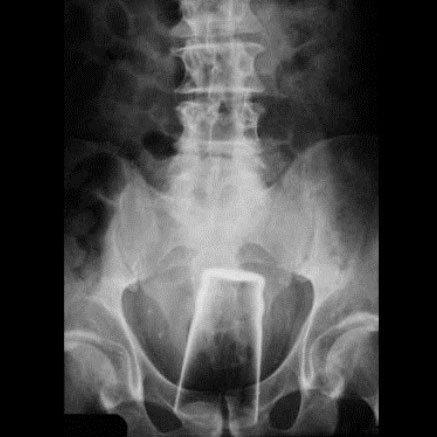

8-Um copo de vidro

De alguma forma essa pessoa conseguiu inserir um copo de vidro dentro de seu corpo sem que ele se quebrasse. Isso deveria ser considerado quase como um teste de resistência da fabricante do copo. O copo tinha 500 ml e felizmente o ocorrido não foi mais trágico. Caso ele tivesse se quebrado lá dentro as consequências seriam realmente críticas.